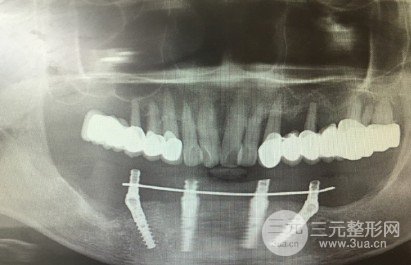

雅博士牙齿种植案例

雅博士口腔医院牙齿种植案例

患者下排牙齿缺失长期,主要佩戴假牙,不适感明X,采用Allon4种植,使用四颗种植体,就能保Z下排牙齿正常的支撑力量。种植后外观美学和功能兼具,咬合功能良好,需要一段时间适应新种植牙齿。